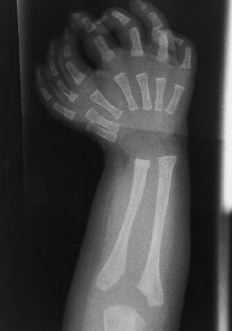

Figura 1. Caso 1. A: Mano derecha con siete dedos. B: Imagen radiográfica de ambas manos; el radio central es algo más grueso y parece el eje de la mano. C: Ambos pies con los cuatro dedos externos normales y aspecto global de pies en espejo.